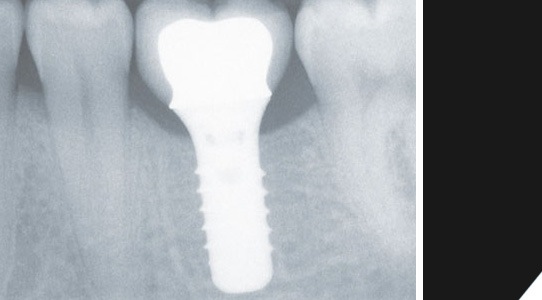

Allein die Röntgenaufnahme verrät, dass es sich hier um ein hochwertiges Titanimplantat handelt.